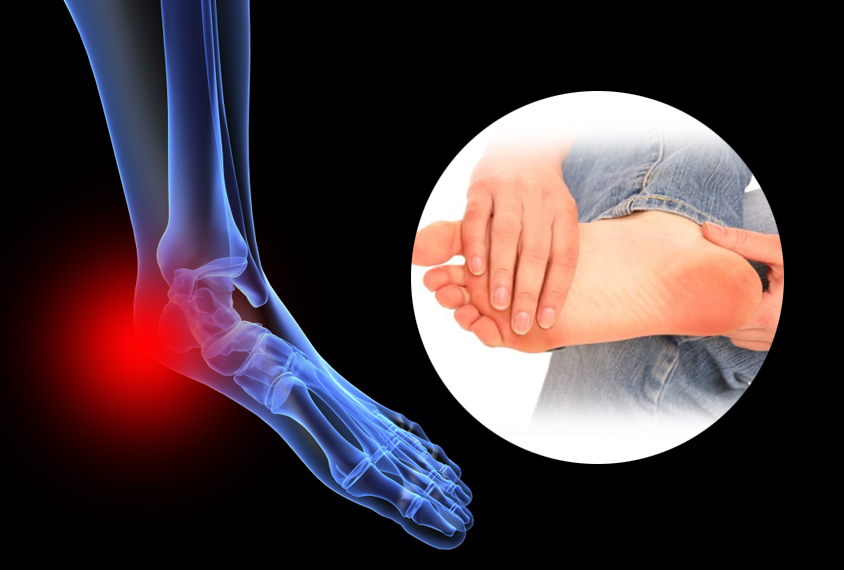

아킬레스건염

- 아킬레스건의 염증으로 인해 발생하는 통증으로, 발뒤꿈치와 발바닥 사이의 연결 부위에 통증이 느껴질 수 있습니다. 주로 격렬한 운동 후, 혹은 운동 부족 후 갑자기 운동을 시작할 때 자주 발생합니다. 통증은 특히 아침에 일어났을 때나 활동을 시작할 때 더 심해질 수 있습니다.

발바닥통증의 원인 발목 염좌

- 발목을 삐거나 부상을 당했을 경우, 발바닥에 통증이 나타날 수 있습니다. 이 경우에는 발목 주위의 부기나 통증이 함께 나타나는 것이 일반적입니다. 발목의 안정성이 떨어지면 발바닥에도 불편함이 전해질 수 있습니다.